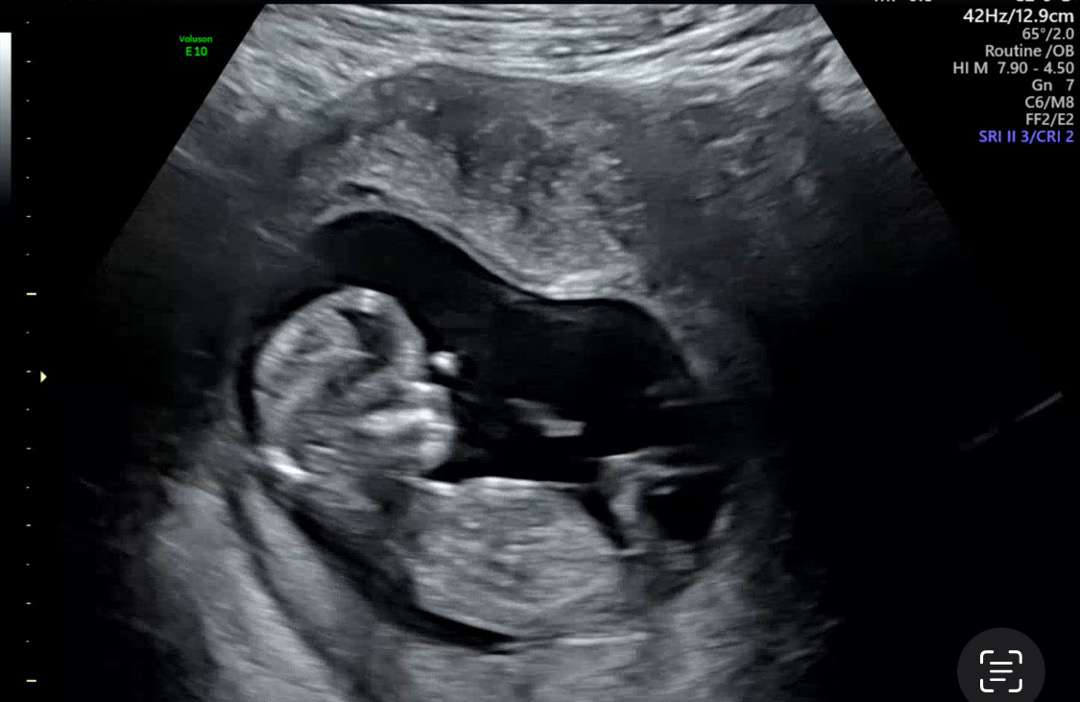

아들입니다.

각도법 한번 봐주세용!!!

아들일까요? 딸일까요?